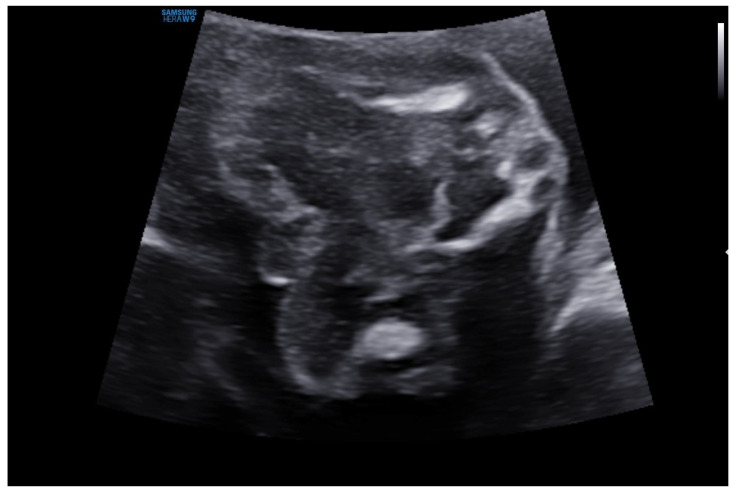

Background and Clinical Significance: The 45,X0/46,XY mosaic karyotype is categorized as a disorder of sex development and can lead to atypical sexual development. Latent mosaicism involving Y chromosomal segments may be much more prevalent than previously assumed, according to a growing number of findings. This primarily depends on how sensitive cytogenetic methods are-such as traditional karyotype screening, FISH methods, or molecular analyses. Case Presentation: We present the case of a 10-week-old infant with hermaphroditic external genitalia. During pregnancy, ultrasonography revealed severe fetal development difficulties, including severe widespread edema. An abnormal 45,X0/46,XY mosaic karyotype was discovered during a genetic amniocentesis conducted during the 16th week of pregnancy. The infant was born in average general condition at 39 + 6 weeks of gestation. Physical examination of the infant revealed features of facial dysmorphia, webbed neck, and hermaphroditic external genitalia. The testicle was palpable on the left side, but the gonad was absent on the right. Laboratory tests revealed a typical hormonal profile of the mini-puberty period in boys. Moreover, a hormone panel and thyroid ultrasound were performed; congenital hypothyroidism was diagnosed. Three separate independent sources of biological material were used in cytogenetic analysis to determine the karyotype: skin fibroblasts (to confirm tissue mosaicism), oral epithelial cells (FISH), and peripheral blood lymphocytes. It showed that a mosaic occurred very early in embryogenesis by confirming the existence of karyotypes 45,X and 46,XY in various tissues (mosaic tissue distribution). Conclusions: Tissue mosaicism should be compared to the analysis of tissues from other embryonic origins, including blood and oral tissue. Support for gender identity and treatment decisions, including the prediction of the future risk of gonadoblastoma, as well as multidisciplinary care, is necessary.